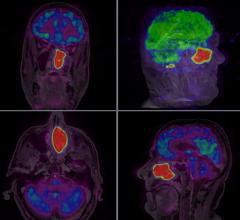

Power injectors with standard, preloaded contrast media protocols are helping to make images more consistent, regardless of the technologist or radiologist using the system. Several years of research by major academic centers has been invested to create these protocols to help CT users with the advanced capabilities of their newer imaging systems. This is especially important for centers using various types of scanners (16-, 64-, 256-slice, etc.), where different protocols are needed based on each scanner type and numerous exam factors, such as the contrast media parameters, rate of injection, volume, organ type being imaged and the patient’s weight.